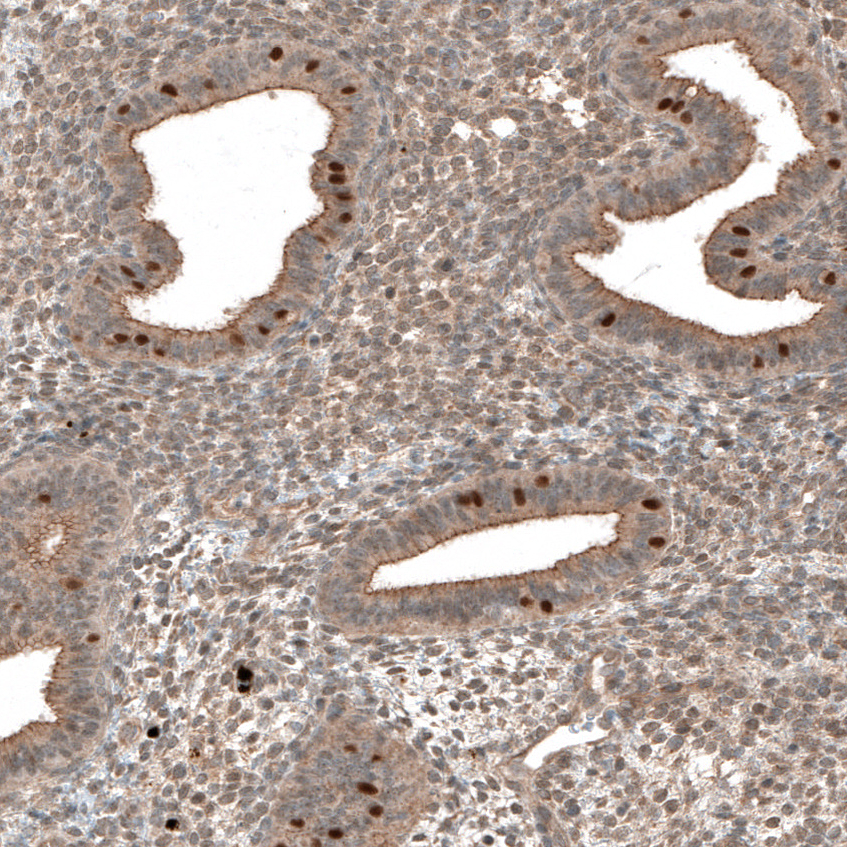

Immunohistochemical staining of human fallopian tube shows strong nuclear positivity in glandular cells.